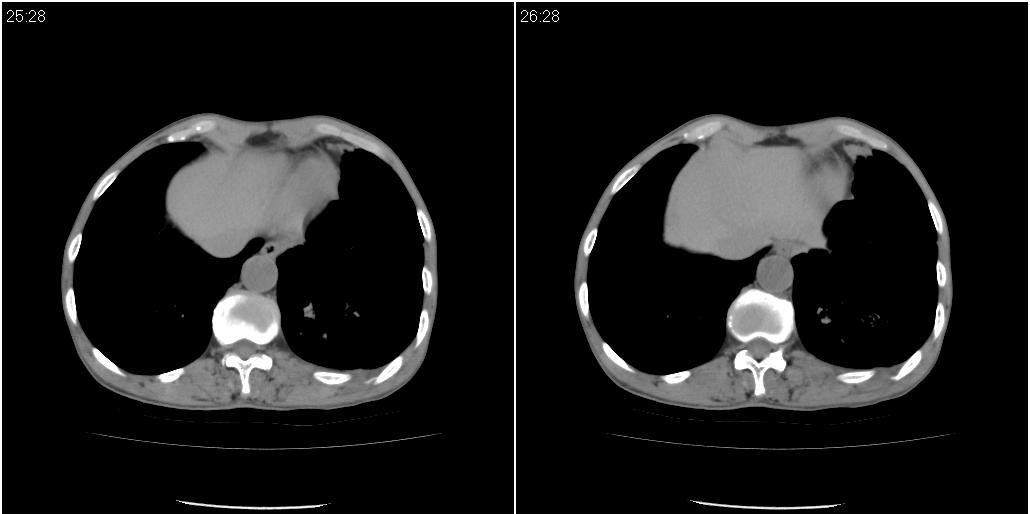

以下是ct检查的情况:

标题: ct增强: